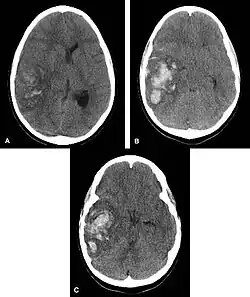

| Multiple intraparenchymal hemorrhage | |

Intraparenchymal hemorrhage is one form of intracerebral bleeding in which there is bleeding within brain parenchyma. The other form is intraventricular hemorrhage).[1]